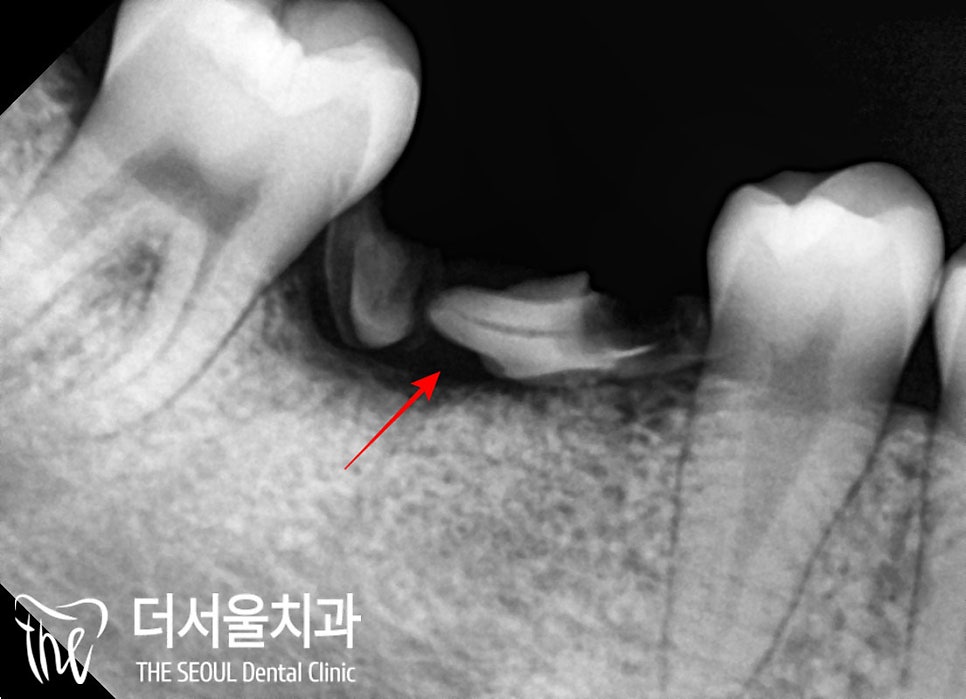

3. 디지털 임플란트

성남 치과 에서는

자연치의 기능을 잃은

어금니를 대체하기 위해

디지털 임플란트를 하기로 했습니다.

CT와 구강 스캔을 이용하여

식립에 필요한 정보들을 취합했는데요,

아랫니는 하치조 신경에 닿지 않도록

윗니는 상악동을 천공시키지 않도록

픽스처의 식립 위치와 깊이를 결정했습니다.

그리고 디지털 임플란트 가이드를 이용하여

빠르고 안전하게 심어드렸습니다.

다행히 골소실이

그렇게 심하지 않아

잔존 치근은 깨끗하게 뽑았으며

원했던 위치에

잘 심어진 것을 확인할 수 있습니다.